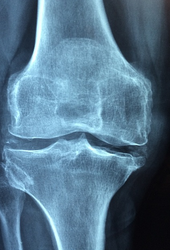

- **관절 건강 개선**: MSM은 관절 통증, 뻣뻣함, 부종을 감소시키고, 관절 연골을 구성하는 콜라겐과 프로테오글리칸의 생성을 촉진합니다. 또한 관절 건강에 도움이 되는 콘드로이틴 설페이트, 보스웰릭산, 글루코사민 설페이트와 같은 성분의 흡수를 돕습니다 .